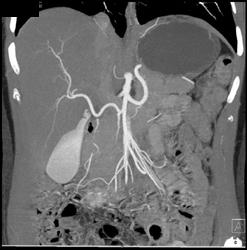

Collaterals Due to Splenic Vein Occlusion Due to Pancreatic Cancer